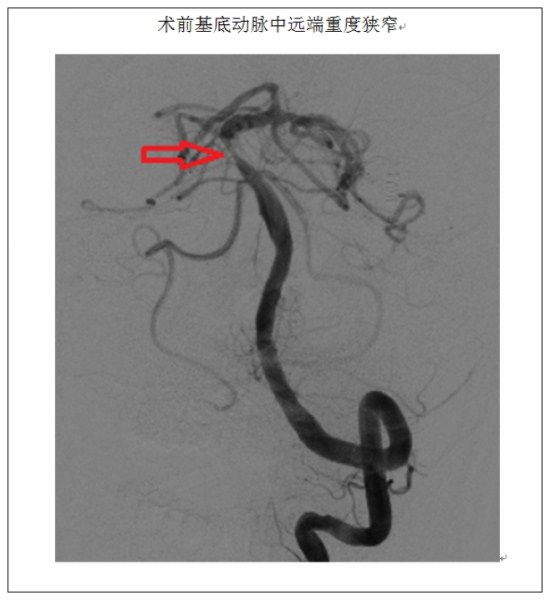

患者66岁,既往有高血压病及糖尿病病史多年,今年3月因“突发意识障碍2小时”在我院脑外科行急诊取栓术,术中造影提示基底动脉及左侧椎动脉重度狭窄。术后患者恢复良好,考虑到患者基底动脉重度狭窄系此次急性脑梗死责任病灶,短期内再发致命性脑干梗死的风险很大,后转入我科行二期介入治疗。患者基底动脉狭窄处穿支血管丰富,对介入治疗技术要求高、风险大、易并发致命性脑干出血或穿支闭塞致脑干梗死;患者的基底动脉及左侧椎动脉开口串联病变,横跨颅内外;左侧椎动脉开口处重度狭窄并迂曲,系手术途径,必须同期治疗。经过充分的术前准备后, 4月3日,患者在全麻下行基底动脉+左侧椎动脉联合支架成形术,术中提示左侧椎动脉70%狭窄,基底动脉远端90%狭窄。经过三个多小时的共同努力,治疗团队于基底动脉及左侧椎动脉开口处各置入一枚支架,术后血管形态及血流通畅程度较术前明显改善。患者现已痊愈出院,住院观察期间无并发症发生。